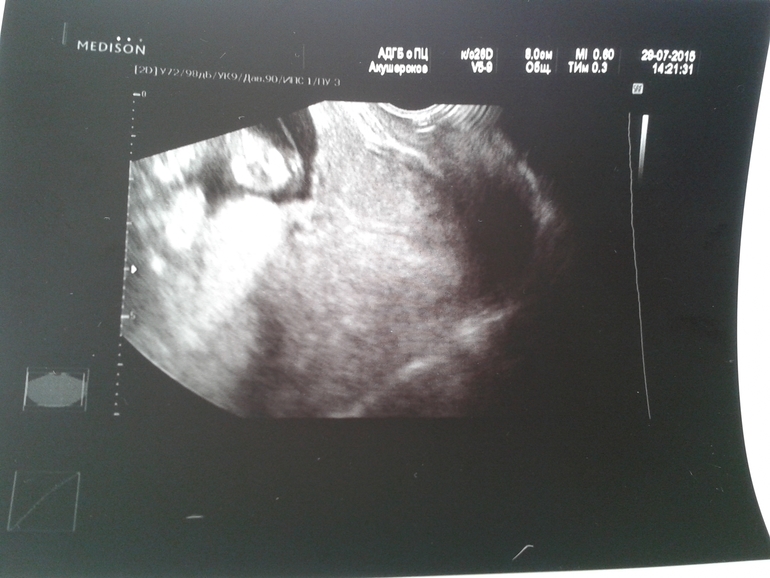

В общем рано я кипишь устроила, насчет укорачения. Сходила я ради спокойствия в платное узи к хорошему врачу, в общем по узи шейка: 49 мм на 28 мм!

Но узист, сказал что у меня краевое

прикрепление плаценты.Что это? И чем это грозит???????

А так зев закрыт!